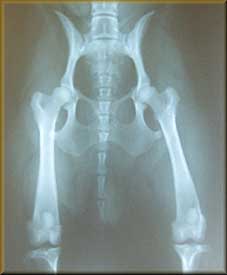

This is Spooky, CH. BlackThorn of Dark Star, CD, WC; she was 31 months old at the time of the x-ray. The consensus on her hips was two grading her hips at a "Fair", and one grading her as a "Good", so her average, and rating, was "Fair". Her OFA # was LR-15970-T - meaning Labrador Retriever #15970 to receive an OFA rating, and the "T" meant that she was tattooed.